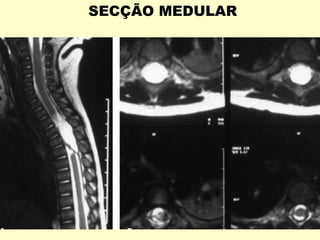

SECÇÃO MEDULAR

Pequeno hematoma epidural C7-T1

Pequeno edema/hematoma de medula cervical C1-C2

12ª SEMANA- MEDULA ESPINHAL E

CANAL VERTEBRAL QUASE IGUAIS.

EVOLUTIVAMENTE O CANAL SE

TORNA MAIOR , DE MODO QUE

OS NERVOS ESPINHAIS TEM UM

CURSO MAIS LONGO PARA ALCANÇAR

O NÍVEL CORRETO.CAUDA EQUINA.

CONE MEDULAR NÍVEL L1-L2 .